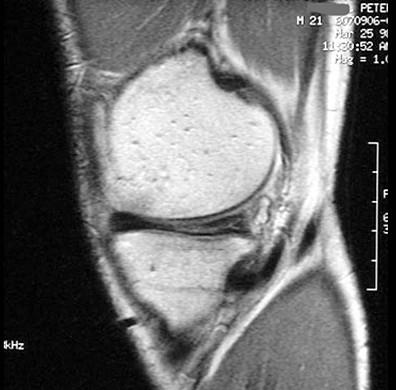

问题 男,21岁,膝关节疼痛,行走困难,曾有外伤史,请结合所提供的图像,选择最佳选项 ( )

选项 A、未见异常 B、前十字韧带撕裂与巨大半月板囊肿 C、内侧半月板撕裂 D、巨大半月板囊肿 E、内侧半月板撕裂与巨大半月板囊肿

答案 E